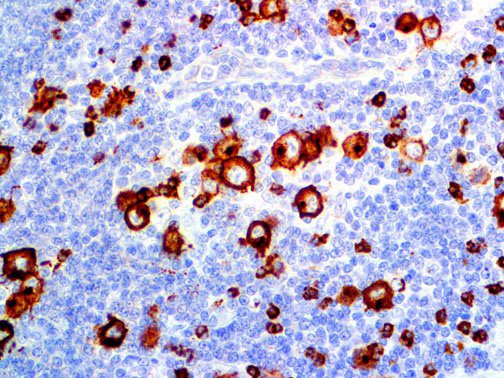

It is the ICU physician who is most likely to witness one of the deadliest manifestations of the abnormal immunological response, the cytokine storm syndrome (CSS). This response is also referred to by some as the cytokine release syndrome (CRS). CSS is characterized by continuous activation and expansion of macrophage and lymphocyte populations, which secrete large amounts of cytokines, causing the cytokine storm. This massive cytokine release is akin to hemophagocytic lymphohistiocytosis (HLH) disease, a syndrome characterized by initial unchecked and persistent activation of cytotoxic T lymphocytes and NK cells.

Clinical and laboratory manifestations of HLH include fever, enlarged liver and/or spleen, neurologic dysfunction, coagulopathy, liver dysfunction, cytopenias (i.e., low levels of erythrocytes, leukocytes, and/or platelets), hypertriglyceridemia, hyperferritinemia, hemophagocytosis, and eventually diminished NK cell activity as the immune system becomes progressively paralyzed. HLH can be familial (primary HLH) or secondary to another disease process (sHLH), such as rheumatic disease, in which it is referred to as macrophage activation syndrome (MAS, characterized by elevated ferritin).